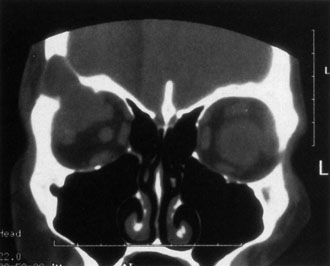

If NFM is suspected, MRI should be ordered of the orbits and brain to exclude noncontiguous intracranial anomalies.93 Magnetic resonance imaging demonstrates the dilated cystic spaces with either a hypointense (lymphatic cyst) or hyperintense (hemorrhagic cyst) signal on T1-weighted images, and a hyperintense signal on T2-weighted images (Fig. 10, A&B).94Layering may be seen within the cysts if there has been a recent hemorrhage leaving unresorbed blood. The CT scans of patients with a deep NFM show low-density, poorly defined masses behind the orbital septum in the extraconal and intraconal spaces, which may indent the globe.3 Calcification within the mass (Fig. 11) and inhomogeneous enhancement of the rim and focal areas within the lesion may be seen that corresponds to abnormal endothelially lined channels.3 Enlargement of the bony orbit can occur, particularly with combined lesions.3,89 If the diagnosis is still unclear, ultrasonography can be performed. A cystic orbital mass is seen on B-scan. A-scan shows features of a solid, cellular tumor: low reflectivity, regular homogeneous internal structure, and marked sound attenuation through the mass.3,89 Standard pulsed Doppler ultrasound confirms no intrinsic flow within the lesions.

Fig. 11. Axial computed tomography scan of patient in Figure 9, showing poorly defined orbital mass with calcifications. (Courtesy of Nancy A. Tucker MD, Illinois Oculoplastic Associates)